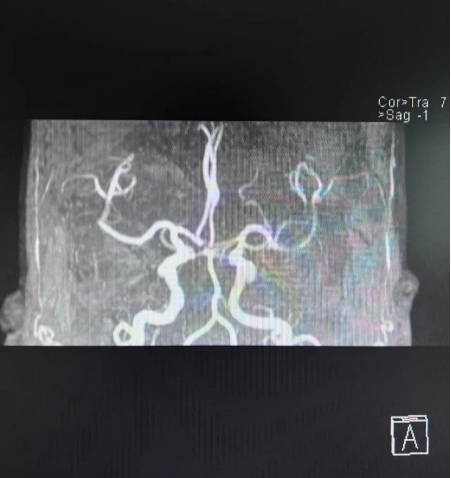

0點(diǎn)24分,張女士在灃東院區(qū)腦病病區(qū)進(jìn)行阿替輔酶靜脈溶栓,DNT時(shí)間35分鐘。1點(diǎn)30分,溶栓治療結(jié)束,患者無明顯不適,生命體征平穩(wěn),NIHSS評(píng)分6分,完善顱腦DWI、MRA,溶栓治療成功。

顱腦DWI、MRA